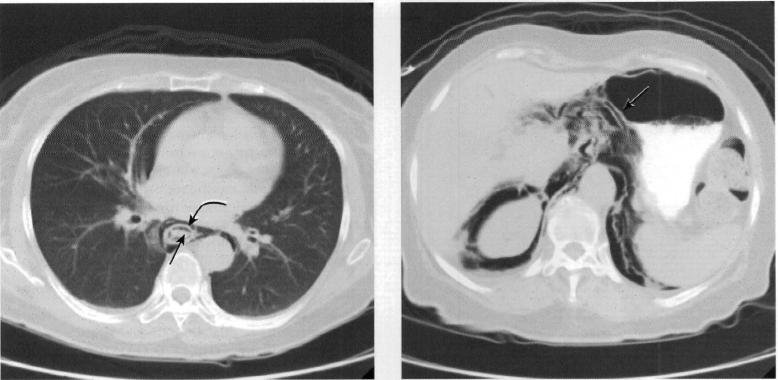

2 anos; masculino; respiração ruidosa desde o nascimento.

Cisto de duplicação esofágico

Predleção por meninos; diagnosticados na infância

Em geral assintomáticos; podem provocar estridor

Mais comuns no esôfago distal; geralmente não comunicam com a luz do esôfago;

TC: Cisto com densidade de líquido, margens bem definidas que podem realçar com contraste; podem complicar com hemorragia, infecção: nível liquido, espessamento parietal.